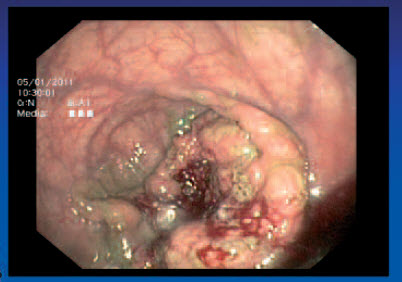

Tumor T3 N1 - kolonoskopie

Tumor T3 N0 - kolonoskopie